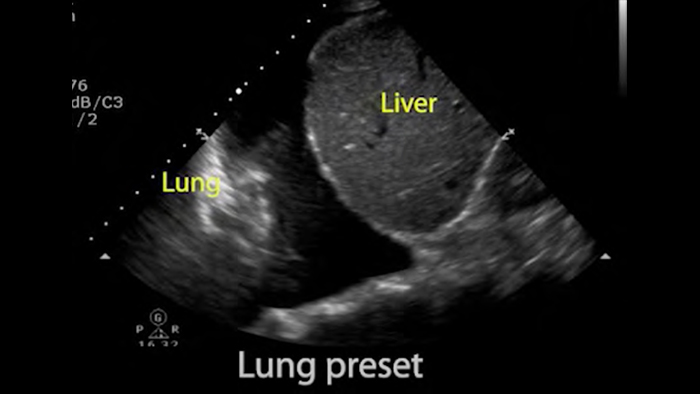

Basisprincipes van longechografie